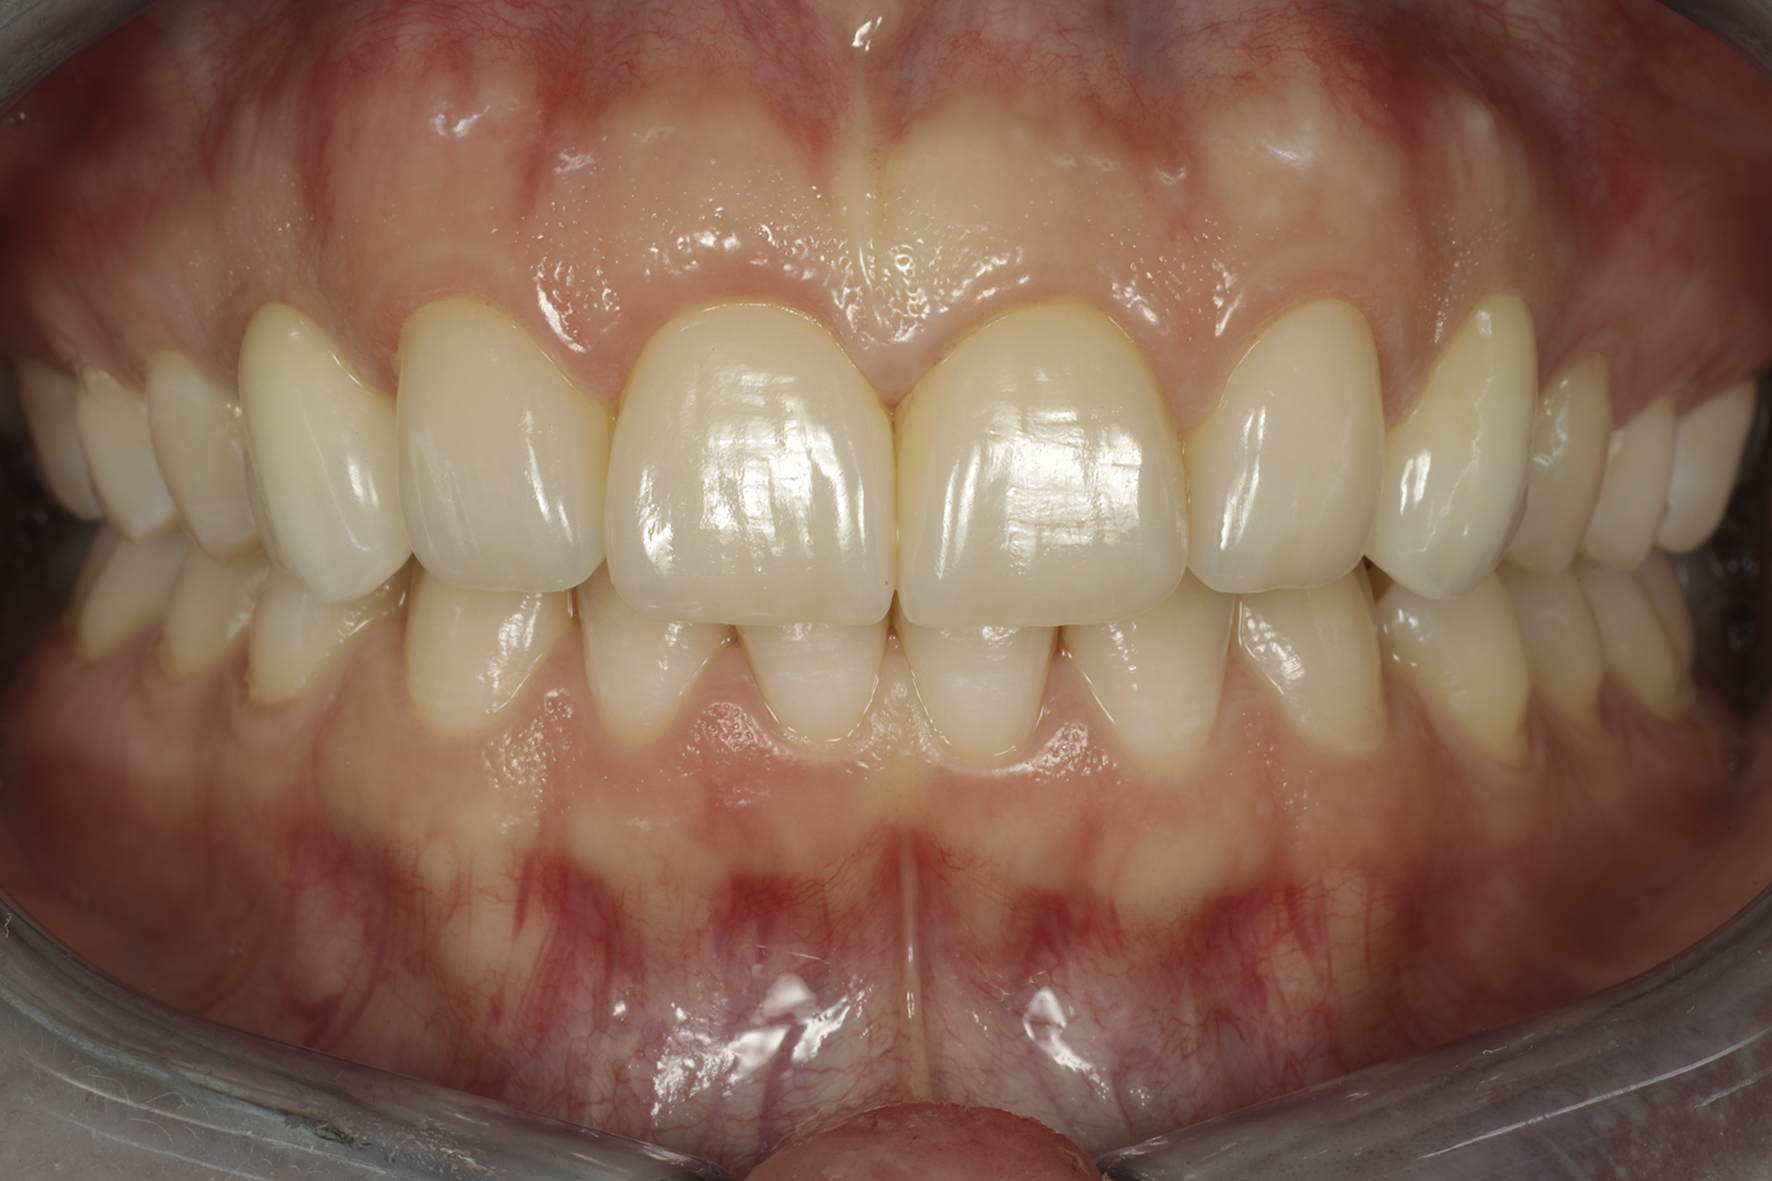

Lopputilanne

Lopputilanne läheltä